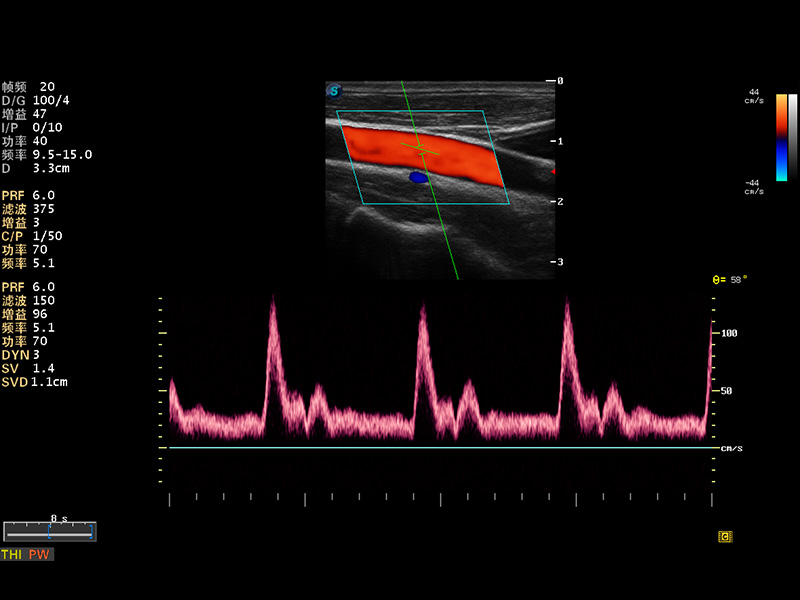

成像技术

多波束形成器